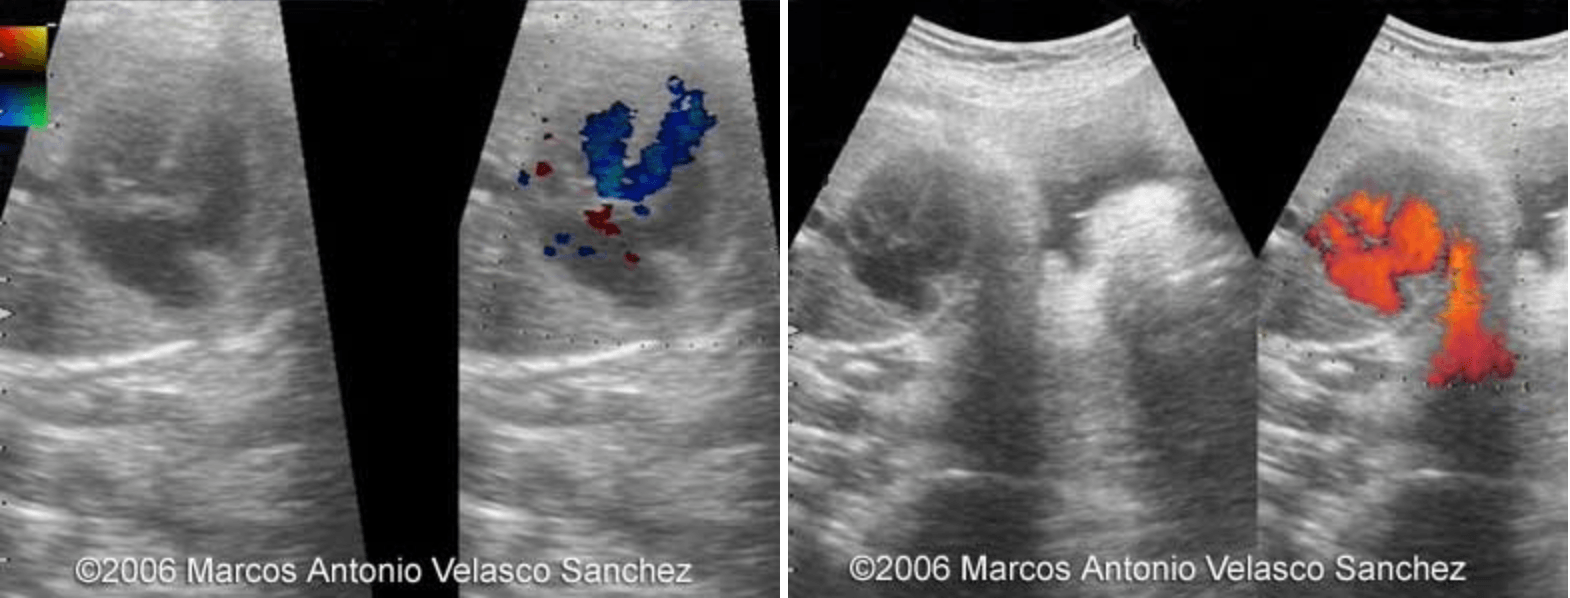

Heart of the fetus